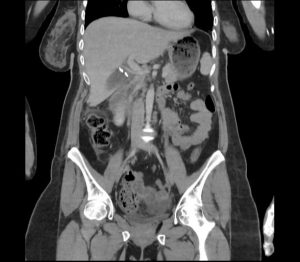

Five days after the operative treatment, the patient experienced severe abdominal pain accompanied by nausea and vomiting. The laboratory results showed elevated white cells count 11.1 (normal range: 4.00-9.00 10/9L), elevated CRP 67.3 (normal range: under 6mg/L), normal total bilirubin 14 (normal range under 20.5umol/L) and elevated direct bilirubin 10.2 (normal range: under 6.8umol/L). Control CT scan of the abdomen with intravenous contrast was performed, where in the region of the gall bladder a dense free liquid collection was observed, around which small free air inclusions were present, the clips of the cystic artery and ductus cysticus were also visible, and a smaller amount of free liquid was present in the pelvis.

An MRCP was performed next, that showed intact common bile duct and intact cystic duct stump. Also, an area of fluid accumulation was noted in the subhepatic space, intraintestinal and in the small pelvis. Subcutaneous oedema in the right lateral abdominal wall was also noted, most likely post operatively.